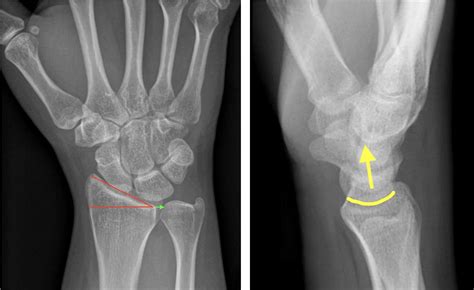

Because hairline fractures are so subtle, they are notoriously difficult to see on standard X-rays, especially in the first few days after an injury. Medical professionals often utilize a combination of clinical physical exams and advanced imaging to confirm the diagnosis.

Standard X-Ray Initial screening to rule out complete breaks or dislocations.